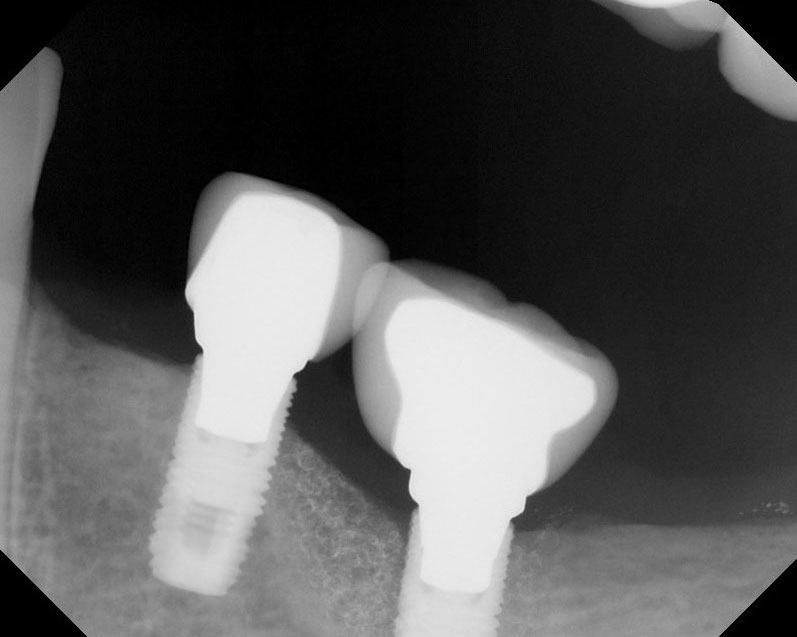

Implants

This treatment involves implanting artificial dental roots, and restoring dental crown without damaging the adjacent teeth.